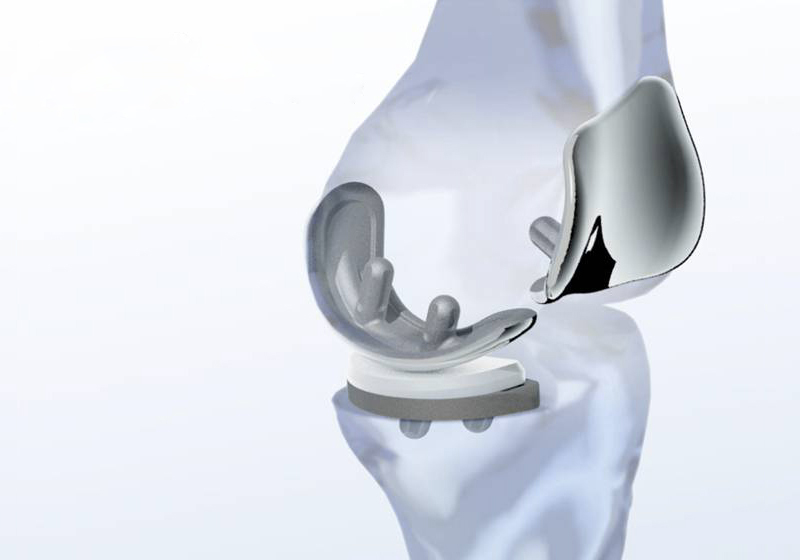

Makoplasty bu robotik kol yardımı ile yapılan girişimlerin tamamını ifade etmektedir. Şu an için total kalça protezi ve unikondiler diz protezi ameliyatları bu robotik uygulamaya açık haldedir.